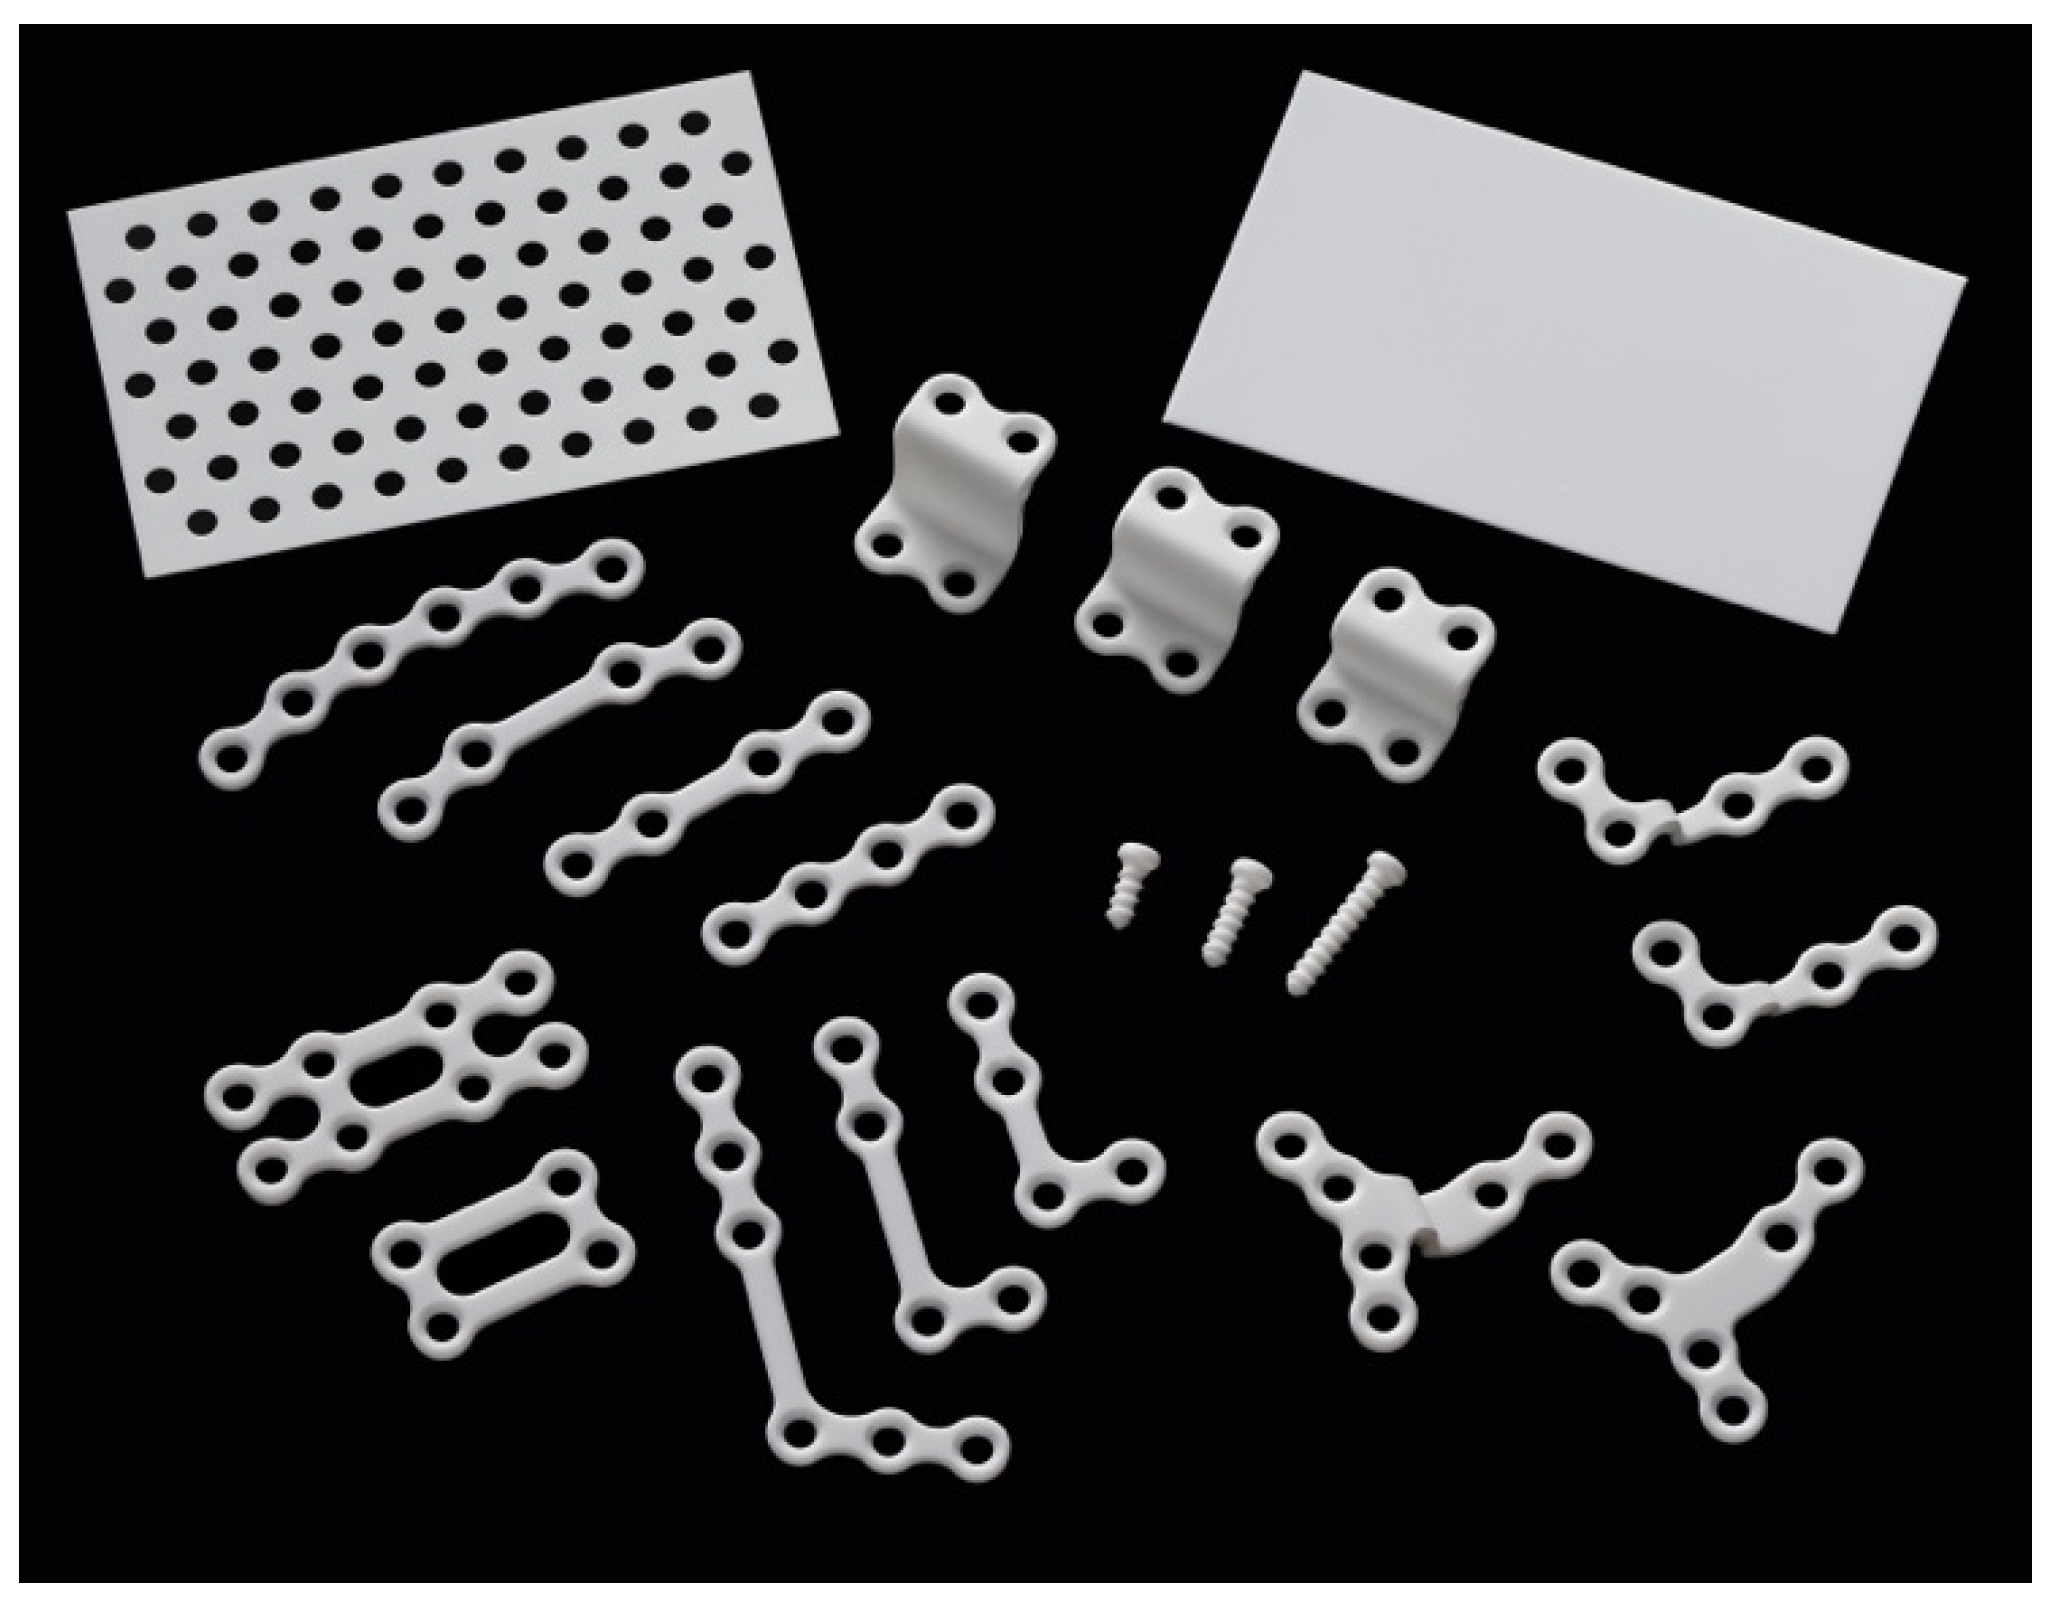

3. Clinical Applications of u-HA/PLLA in Oral and Maxillofacial Surgery

3.1. Maxillofacial Trauma

3.1.1. Orbital Wall Fractures

3.1.2. Midfacial Fractures

3.1.3. Mandibular Fractures

3.2. Orthognathic Surgery

3.2.1. Le Fort I osteotomy

3.2.2. Mandibular Osteotomies

3.3. Other Reconstructive Applications